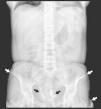

Mujer de 36 años con antecedente de lupus eritematoso sistémico de 21 años de evolución, con afectación hematológica, cutánea y articular. En el estudio inmunológico destacan ANA (título 1:1.000, patrón de fluorescencia homogéneo), anti-DNA, anti-ENA y anti-Ro (SSA) positivos. Presenta múltiples nódulos subcutáneos de consistencia dura en tronco y extremidades de aproximadamente 10 años de evolución, que confluyen en cintura, glúteos y muslos formando extensas placas. A lo largo del último año, refiere la aparición progresiva de una úlcera con exudado seroso sobre una de las lesiones en muslo izquierdo. Los cultivos resultaron positivos para Staphylococcus aureus. La radiografía simple de abdomen (fig. 1) y una tomografía computarizada abdominal (fig. 2) revelaron múltiples calcificaciones extraóseas (flechas) de localización subcutánea. A pesar del tratamiento con diltiazem, las calcificaciones persisten y la lesión ulcerosa presenta una evolución tórpida.